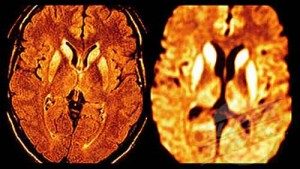

Interagendo con la proteina prionica“sana”, il glicolipide GM1 aumenta le probabilità che assuma la forma “tossica”, causa delle encefalopatie spongiformi...

Un nuovo test del sangue ha mostrato di riuscire a evidenziare proteine malformate che sono legate alla forma umana del...

Una improvvisa perdita di udito da entrambi i lati puo' essere un sintomo del morbo di Creutzfeldt-Jakob, una patologia della...